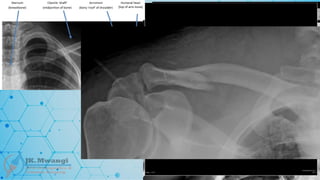

Colles fracture

 A fracture of the distal radius with dorsal (upward) displacement, often resulting

from a fall onto an outstretched hand. Named after Abraham Colles, who first

described the fracture in 1814.

Smiths fracture

 A distal radius fracture, but with volar (downward) displacement, often described

as the reverse of Colles' fracture. Named after Robert William Smith in 1847